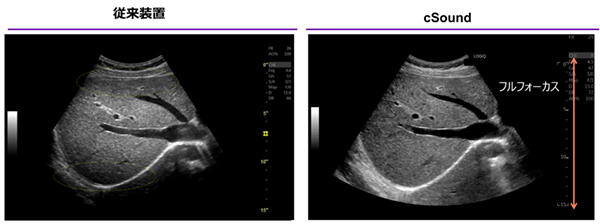

特長<1>

全視野・全深度フルピクセルフォーカス

高性能GPUを搭載し,多方向から膨大に受信・蓄積した超音波データをリアルタイムに再構成。1ピクセルごとに焦点を合わせることに成功した。 フレームレートは高いまま,高分解能の画像が得られ,造影もフルフォーカスを実現している。